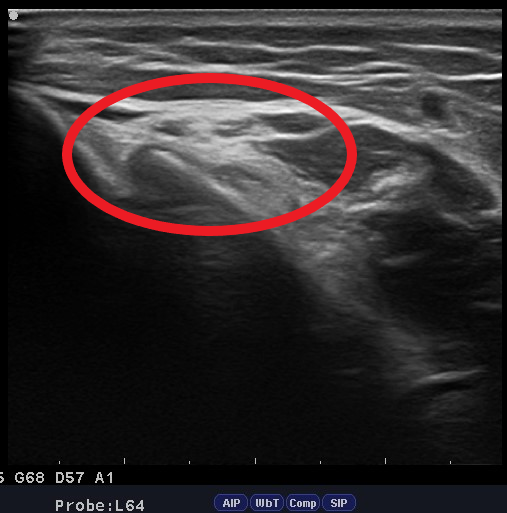

47歳 男性 両肘の痛み

当院来院時

左:患側

右:スタッフ健常者の肘

1週間前より両肘に痛み出現。

ベンチプレストレーニングをした翌日に痛み増悪するため、当院来院。

エコー観察にて関節内の水腫があると判断。

トレーニングを2週間休止するよう指示。